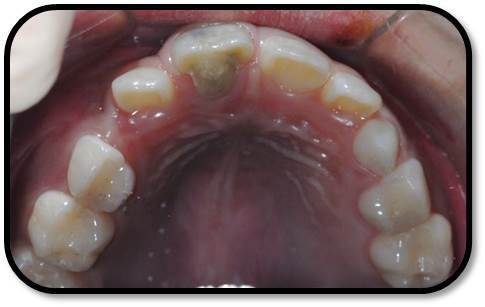

检查: 右上1牙冠略宽大,舌侧见粗大的畸形舌尖,叩痛(++),松Ⅰ°,唇侧牙龈红肿前庭沟膨隆扪痛,挤压唇侧龈缘溢脓,冷热测无反应,右侧上下1侧方颌,正中颌颌创伤。 X线:右上1发育7-8期,根管平行状,根尖孔宽大,约5-6mm宽,根尖周低密度影。髓腔根管宽大内见倒置牙影像,倒置牙可见髓腔。 余牙未见异常 6均已萌出建颌

初步诊断:右上1牙内陷根尖炎,颌创伤 治疗计划:1、口腔卫生宣教 2、右上1调合,牙髓再血管化治疗, 成年后烤瓷贴面修复 3、定期复查(1月、3月、6月--) 处置:右上1STA必兰局麻下舌侧开髓,查得两根管,一个是长扁根管,一个是牙中牙内陷盲袋形成的椭圆根管,拔根髓不成形,5.25%次氯酸钠冲洗浸泡根管5-10分钟,超声根管荡洗,反复3次,2%CR冲洗根管,隔湿干燥后,封Ca(OH)2。调合,去除咬颌创伤。 复诊:隔2周复诊,行5.25%次氯酸钠冲洗浸泡根管5-10分钟,超声根管荡洗,反复3次,2%CR冲洗根管,隔湿干燥后,封Ca(OH)2。 此后复诊每隔1周行2.5%次氯酸钠冲洗浸泡根管5-10分钟,超声根管荡洗,反复3次,2%CR+NS冲洗根管,隔湿干燥后,封Ca(OH)2。 2个月后:患牙症状消失,临床检查无阳性体征,去暂封无渗出,2.5%次氯酸钠冲洗浸泡根管5-10分钟, 2%CR+NS冲洗根管,隔湿干燥后,用无菌30#根管锉超出根尖3-4mm刺破根尖组织出血,待形成血凝块后,置MTA,GIC,冠方树脂严密充填。

随访复查: 治疗完成后1个月复查:右上1临床检查无阳性体征,叩痛(—),冷测无反应,无松动,牙龈无红肿,充填物完好,牙冠略有变色, X线检查:牙根根继续发育,可见钙化影像形成,如图示 治疗完成后7个月复查:临床检查无阳性体征,充填物完好,牙冠变色局部发黑,叩痛(—),冷测无反应,无松动,牙龈无红肿,临床及 X线检查:牙根继续发育,如图示 治疗完成后17个月复查:临床检查无阳性体征,充填物完好,牙冠变色局部发黑,叩痛(—),冷测无反应,无松动,牙龈无红肿。X线:牙根继续发育,根尖孔已近闭合。如图。 讨论: